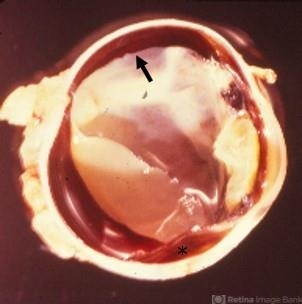

- Nongranulomatous uveitis is a group of diseases often related to systemic autoimmune diseases such as arthritis. In this enucleation specimen, the choroid is diffusely thickened (arrow) and a choroidal detachment is present (*). The retina is opaque and the lens is cataractous.